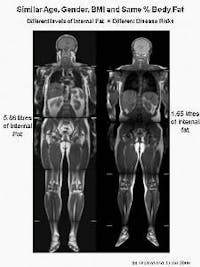

A continuación verás ocho ejemplos de hombres que tienen la misma circunferencia de cintura.

Así que perder centímetros de cintura es un marcador maravilloso de mejoras en la salud metabólica. Pero no siempre se puede confiar en el número real de centímetros. No supongas que una persona es saludable o que no tiene diabetes de tipo 2 solo porque tiene una circunferencia de cintura que no esté dentro de los criterios del síndrome metabólico.